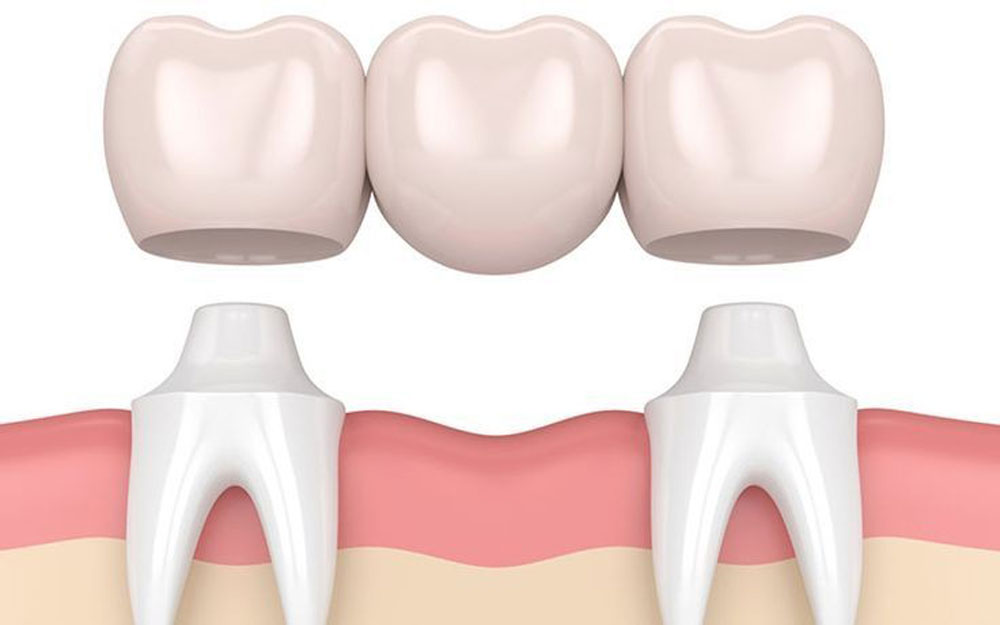

2- بریج یا پل دندانی

بریج دندانی (که به آن پل دندانی نیز گفته میشود) یکی از روشهای رایج برای جایگزینی دندانهای از دست رفته است. این روش شامل اتصال دندانهای مصنوعی به دندانهای سالم مجاور محل دندان از دست رفته است. در واقع، بریج دندانی یک پل است که دندانهای مصنوعی به دندانهای سالم دو طرف محل خالی متصل میشود تا جایگزین دندانهای از دست رفته شود.

انواع بریج دندانی:

- بریج سنتی: این نوع بریج رایجترین نوع است که شامل یک یا چند دندان مصنوعی است که توسط دندانهای سالم دو طرف محل خالی نگه داشته میشود. دندانهای کناری معمولاً نیاز به تراش دارند تا بریج به آنها متصل شود.

- بریج کانتیلورت (Cantilever Bridge): این نوع بریج برای زمانی که فقط یک دندان سالم در کنار محل خالی وجود دارد، استفاده میشود. در این روش، فقط یک طرف بریج به دندان سالم متصل میشود.

- بریج مریلند (Maryland Bridge): این نوع بریج معمولاً برای جایگزینی دندانهای جلویی استفاده میشود. در این روش، دندان مصنوعی به دندانهای مجاور با استفاده از یک فریم فلزی یا سرامیکی متصل میشود و نیازی به تراش دندانهای مجاور نیست.

- بریج پیچشونده (Resin-Bonded Bridge): این نوع بریج بیشتر برای دندانهای جلویی استفاده میشود. دندانهای مصنوعی به دندانهای مجاور با استفاده از چسبهای دندانی قوی متصل میشوند.

بریج دندانی یک گزینه مؤثر برای جایگزینی دندانهای از دست رفته است، اما ممکن است در برخی موارد مانند نیاز به تراش دندانهای سالم و محدودیت در طول عمر، مناسب نباشد. بسته به شرایط دندانی و نیازهای فردی، انتخاب روش صحیح بسیار مهم است.